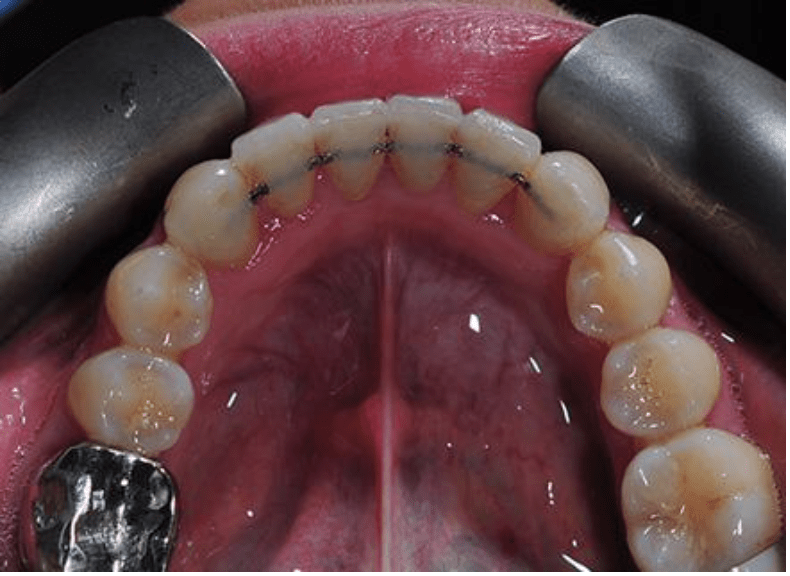

This case took under 12 months to straighten the very crooked teeth in the lower jaw and align the uppers as well. The finished photos show a fixed permanent wire on the inside of the teeth to stop them relapsing or moving back. Permanent wire retainers and night-time removable retainers are always recommended.